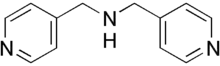

Gapicomine (INN) is a coronary vasodilator. It has been withdrawn from the market in the countries it was used in.[1]

Also, gapicomine is a major component in the drug Bicordin.[2]